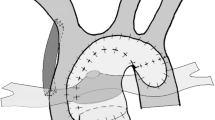

In the most common management strategy of classic HLHS, a series of complex surgeries starting in the neonatal period culminates in the univentricular Fontan circulation. The newborn is maintained on a continuous infusion of intravenous prostaglandin to maintain ductal patency until the Norwood stage 1 operation (Fig. 1), which is typically performed within the first week of life for those without delayed diagnosis. The goals of the Norwood procedure are to restore reliable systemic blood flow while protecting the pulmonary vascular bed. This is accomplished by division of the main pulmonary artery, anastomosis of the ascending aorta to this segment, and reconstruction of a “neo-aorta” to receive the RV output. Controlled blood flow is provided to the now isolated pulmonary arteries through either a modified Blalock-Taussig shunt or RV-to-pulmonary artery shunt [14, 15]. An atrial septectomy is performed to allow unobstructed left-to-right flow.

In most centers the Norwood stage 1 operation is the first intervention for classic HLHS, with a modified Blalock-Taussig shunt (a) or an RV-to-pulmonary artery shunt (b) supplying pulmonary blood flow. Some centers utilize the “Hybrid” approach (c), which includes stenting of the ductus arteriosus and bilateral pulmonary artery banding

The “Hybrid” approach (Fig. 1) has been employed as the first stage of HLHS palliation in some centers, while most have reserved it for neonates with major extracardiac anomalies or complicating factors such as low birth weight or prematurity [16, 17]. The Hybrid procedure currently involves stenting of the ductus arteriosus (via sternotomy) and bilateral pulmonary artery banding to protect the pulmonary vasculature. Retrograde arch obstruction is a complication that occurs in 24–29 % of patients (especially those with aortic atresia) after this approach, and has been identified as a risk factor for morbidity and mortality [18, 19]. Initial enthusiasm for the Hybrid technique as a means of avoiding the sequelae of neonatal cardiopulmonary bypass was tempered by equally high mortality rates [6, 16, 17].